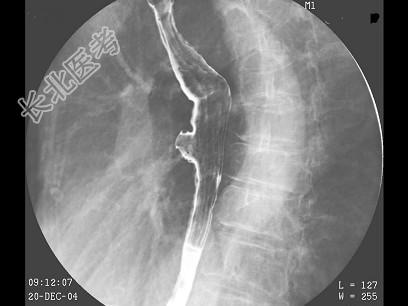

- 多项选择题女,80岁, 胃胀痛20多天,体检: 剑突下有压痛,结合图像, 最可能的诊断为 ( )

A、食管憩室

B、食管癌

C、胃炎

D、胃下垂

E、球部溃疡